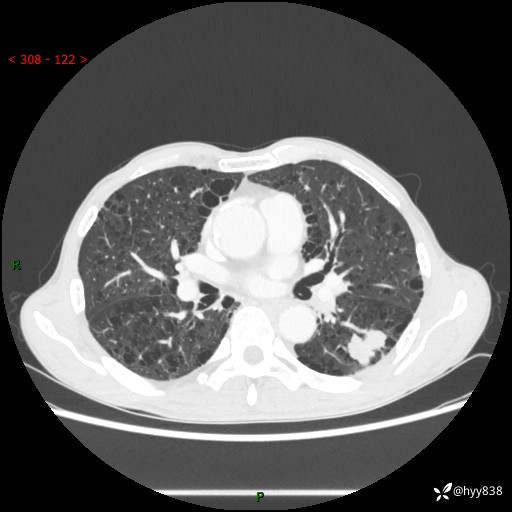

73岁/男,发现肺占位1月余。肺气肿背景,是否恶性倾向---结果公布~

现病史:患者于1月余前无明显诱因出现背部疼痛不适,无明显咳嗽、咳痰、胸闷、咯血、发热等不适,后于2024.5.3至当地市人民医院行胸部CT示:左肺下叶结块,大小约2.2cm*2.6cm,双肺多发小结节,双肺感染性病变,部分纤维增值灶,慢支并双肺局限性肺气肿,肺大泡,纵隔淋巴结增大并部分钙化,冠脉区及大血管壁钙化,双侧胸膜局限性增厚;后口服莫西沙星2周。2024.6.12复查胸部CT示:左肺下叶结块影形态较前饱满,较大截面范围约2.8cm*2.3cm,边缘可见细短毛刺及分叶,性质待查。现患者为求进一步诊治来我院,门诊以“肺占位”收入我科。 起病来,患者精神、食欲、睡眠尚可,大小便正常,体力体重轻微下降。

胸部CT平扫+增强

各期CT值:48hu 100hu 78hu